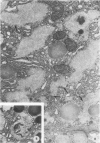

The pathogenesis of a spontaneously occurring exocrine pancreatic insufficiency (EPI) syndrome in CBA/J mice was studied at the ultrastructural level. Initial cytologic manifestations of this syndrome are seen as a progressive digestion of the zymogen granules, beginning at the periphery and proceeding toward the granule interior. Granule membrane breakdown, fusion of neighboring granules, and a release of zymogen contents into the cytoplasm are frequently observed in later stages; in some cases the entire granule contents appear digested before membrane breakdown is observed. In either case, pathologic changes are subsequently observed in mitochondria and rough endoplasmic reticulum. Remnants of lysed cells are then engulfed by invading macrophages, and infiltration by fat cells is observed. Secretory ducts and islets of Langerhans show no pathologic changes even after total autolysis of the exocrine pancreas. Morphologic evidence showing zymogen granule destabilization, coupled with biochemical evidence presented in an accompanying paper, indicate that intracellular autodigestion is the mechanism of exocrine cell death.